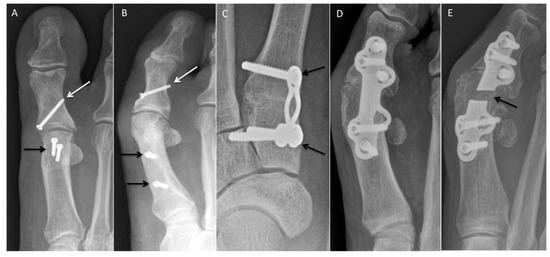

5.1. Polyvinyl Alcohol Hydrogel Hemiarthroplasty/Synthetic Cartilage Implant (SCI)

5.2. Silastic Implant